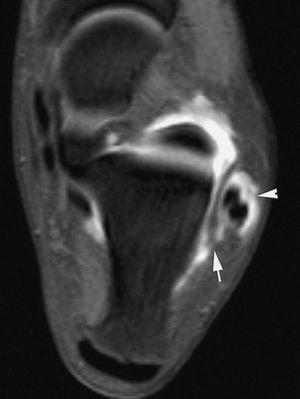

El choque antero-medial es una causa muy infrecuente de dolor crónico de tobillo que está producido por una lesión meniscoide formada por engrosamiento de partes blandas anterior a los fascículos tibio-astragalinos del ligamento deltoideo. La lesión meniscoide antero-medial puede aparecer aislada o asociarse con desgarros parciales del componente profundo del ligamento deltoideo. Otra causa de choque antero-medial es el engrosamiento del ligamento tibio-astragalino anterior. Este engrosamiento o la lesión meniscoide choca con la vertiente antero-medial del astrágalo en la dorsiflexión del tobillo conduciendo a la formación de osteofitos, lesiones condrales o a ambos. La RM convencional no ha mostrado utilidad para detectar las lesiones de choque medial. La RMA es el método diagnóstico de elección, definiendo con claridad la lesión meniscoide medial, el engrosamiento de ligamento tibio-astragalino anterior y cualquier lesión condral u osteocondral asociada19,23.

El choque postero-medial es una causa muy frecuente de dolor en la vertiente postero-medial del tobillo; tras un traumatismo severo por inversión las fibras tibio-astragalinas posteriores del componente profundo del ligamento deltoideo se pinzan entre la cara medial del astrágalo y el maléolo interno. Una inadecuada curación de las fibras contundidas de ligamento tibio-astragalino posterior conduce al desarrollo de fenómenos inflamatorios crónicos, hiperplasia fibrosa y metaplasia. En estos casos el tejido cicatricial puede chocar entre el muro medial del astrágalo y el margen posterior del maléolo interno. La RMA puede mostrar el engrosamiento de partes blandas y evidenciar edema óseo en el maléolo medial y en la cara medial del astrágalo19,23.